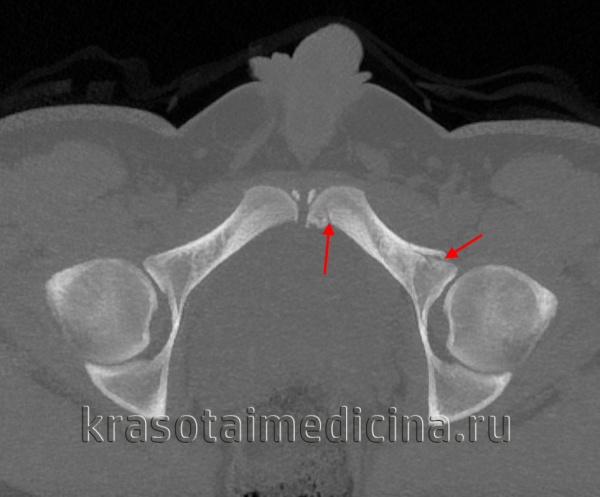

- Компьютерная томография.